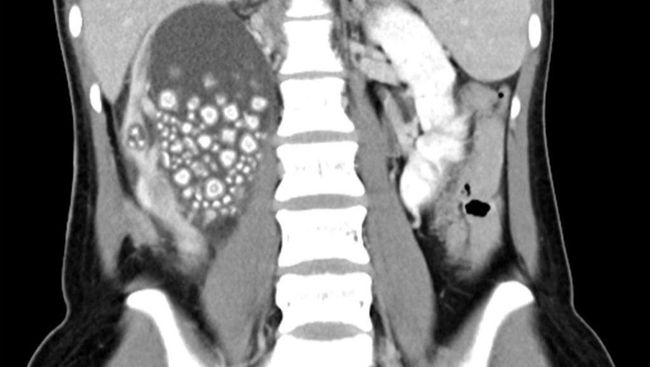

Batu ginjal merupakan endapan keras akibat penumpukan mineral dan garam yang terbentuk di ginjal atau saluran kemih. Penyebab terbentuknya batu ginjal pun bermacam-macam. mulai dari pola makan yang kurang sehat hingga berat badan berlebih